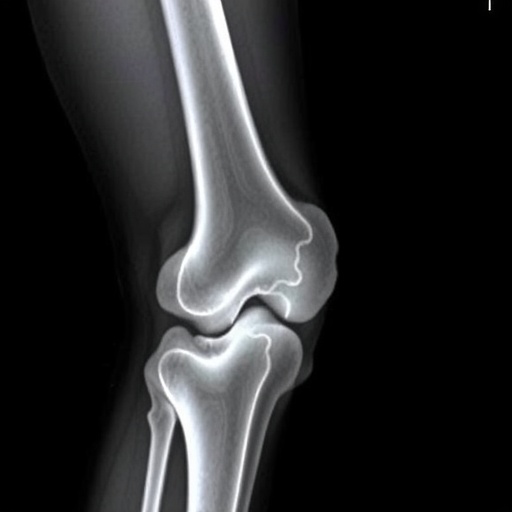

Recent advancements in radiological research have focused on the intricate variations that occur in the metaphyseal regions of long bones, particularly within the distal femurs and proximal tibias. This observational study illuminates the vital importance of accurately distinguishing these subtle anatomical differences from classic metaphyseal lesions often associated with pediatric pathologies. The research, conducted by a team led by Karmazyn et al., lays the groundwork for further exploration in diagnosing conditions involving these critical areas of the skeletal system.

Metaphyseal lesions are typically associated with conditions such as metabolic bone diseases, trauma, and various malignancies. Understanding their anatomical nuances is crucial for clinicians, as misinterpretation can lead to misdiagnosis and inappropriate management strategies. The study makes a compelling argument for the need to refine diagnostic criteria that separate the variations specific to normal anatomy from those that indicate pathology. This improved understanding will significantly impact clinical practices, particularly in pediatric radiology.

Subject of Research: Metaphyseal variations in distal femurs and proximal tibias

Article Title: Can metaphyseal variations in the distal femurs and proximal tibias be distinguished from classic metaphyseal lesions?